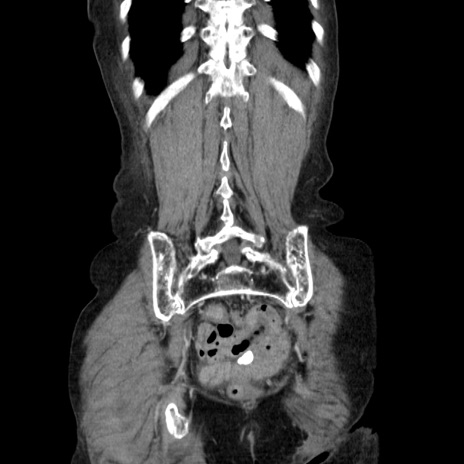

症例25(冠状断像)